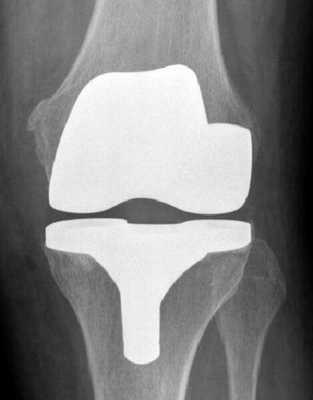

Имплант на рентгене.

Как это выглядит после операции.

Макет импланта коленного сустава.

Рентген после операции. Протез стоит корректно.